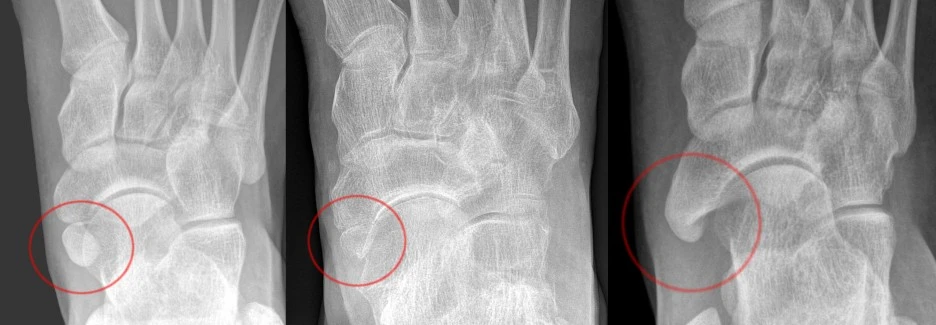

576px-Acessory_Navicular_Bone_2.jpg?type=w1 이렇게 좌우측의 주상골부분에서 융기된 부분을 발견하게 됩니다.

Os_tibiale_externum_Typen_1_-_3_nach_Geist_-_Roe.jpg?type=w1 부주상골의 경우 지속적인 충격이 누적되면서 분리되어 골편으로 존재하게 됩니다. 특히 후경골근이 제 기능을 하지 못하게 되면서 발의 내구성은 떨어지게 됩니다.